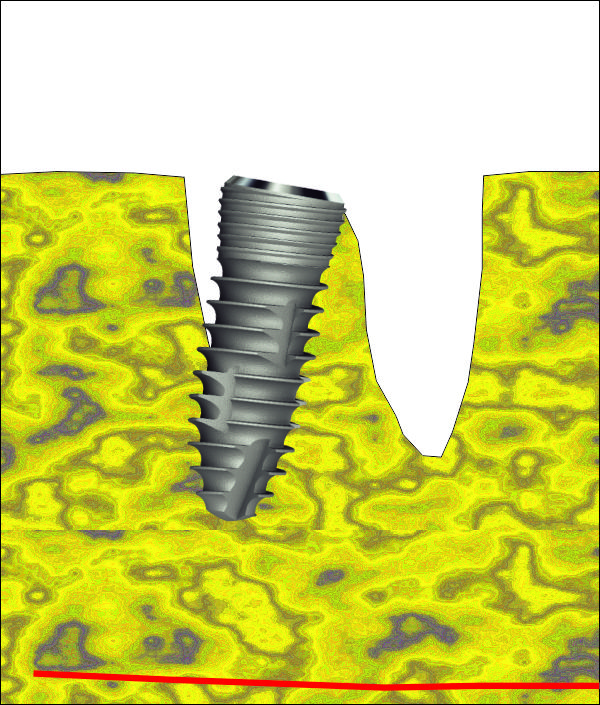

Имплантатът е поставен в костта. Вижда се покривният винт, който е оцветен в синьо. В периферията се вижда т.нар. bevel design на имплантатите - скосен дизайн, който улеснява работата на имплантолога и най-вече на вносителя на имплантатната система. Улеснението е голямо - скосеният дизайн позволява да се прилагат универсални надстройки за по-тесни и по-широки импланти. Освен това скосяването на имплантата предпазва от костна загуба - възпалителният инфилтрат от операцията мигрира над импланта и медиаторите на възпалените упражняват своето действие там. Някои от тези медиатори могат да причинят тъканна автолиза; очевидно не е възможно да разрушат титана. Повече информация за вътрекостните импланти... При гореописаната клинична ситуация е напълно възможно да се изчака много кратък оздравителен период и да се постави надстройка и корона, т.е. да се извърши имедиатно имплантиране + имедиатно натоварване. Така и постъпихме в случая. Спрямо научните схващания от 80-те и началото на 90-те години това е звучало като ерес и е било достатъчно основание извършителят да бъде разпънат на кръст, изгорен на клада или обесен, а понякога и двете заедно; в днешно време обаче има достатъчно натрупани клинични наблюдения и до голяма степен такъв тип лечение се превръща в стандартна процедура. Вход в нашия форум